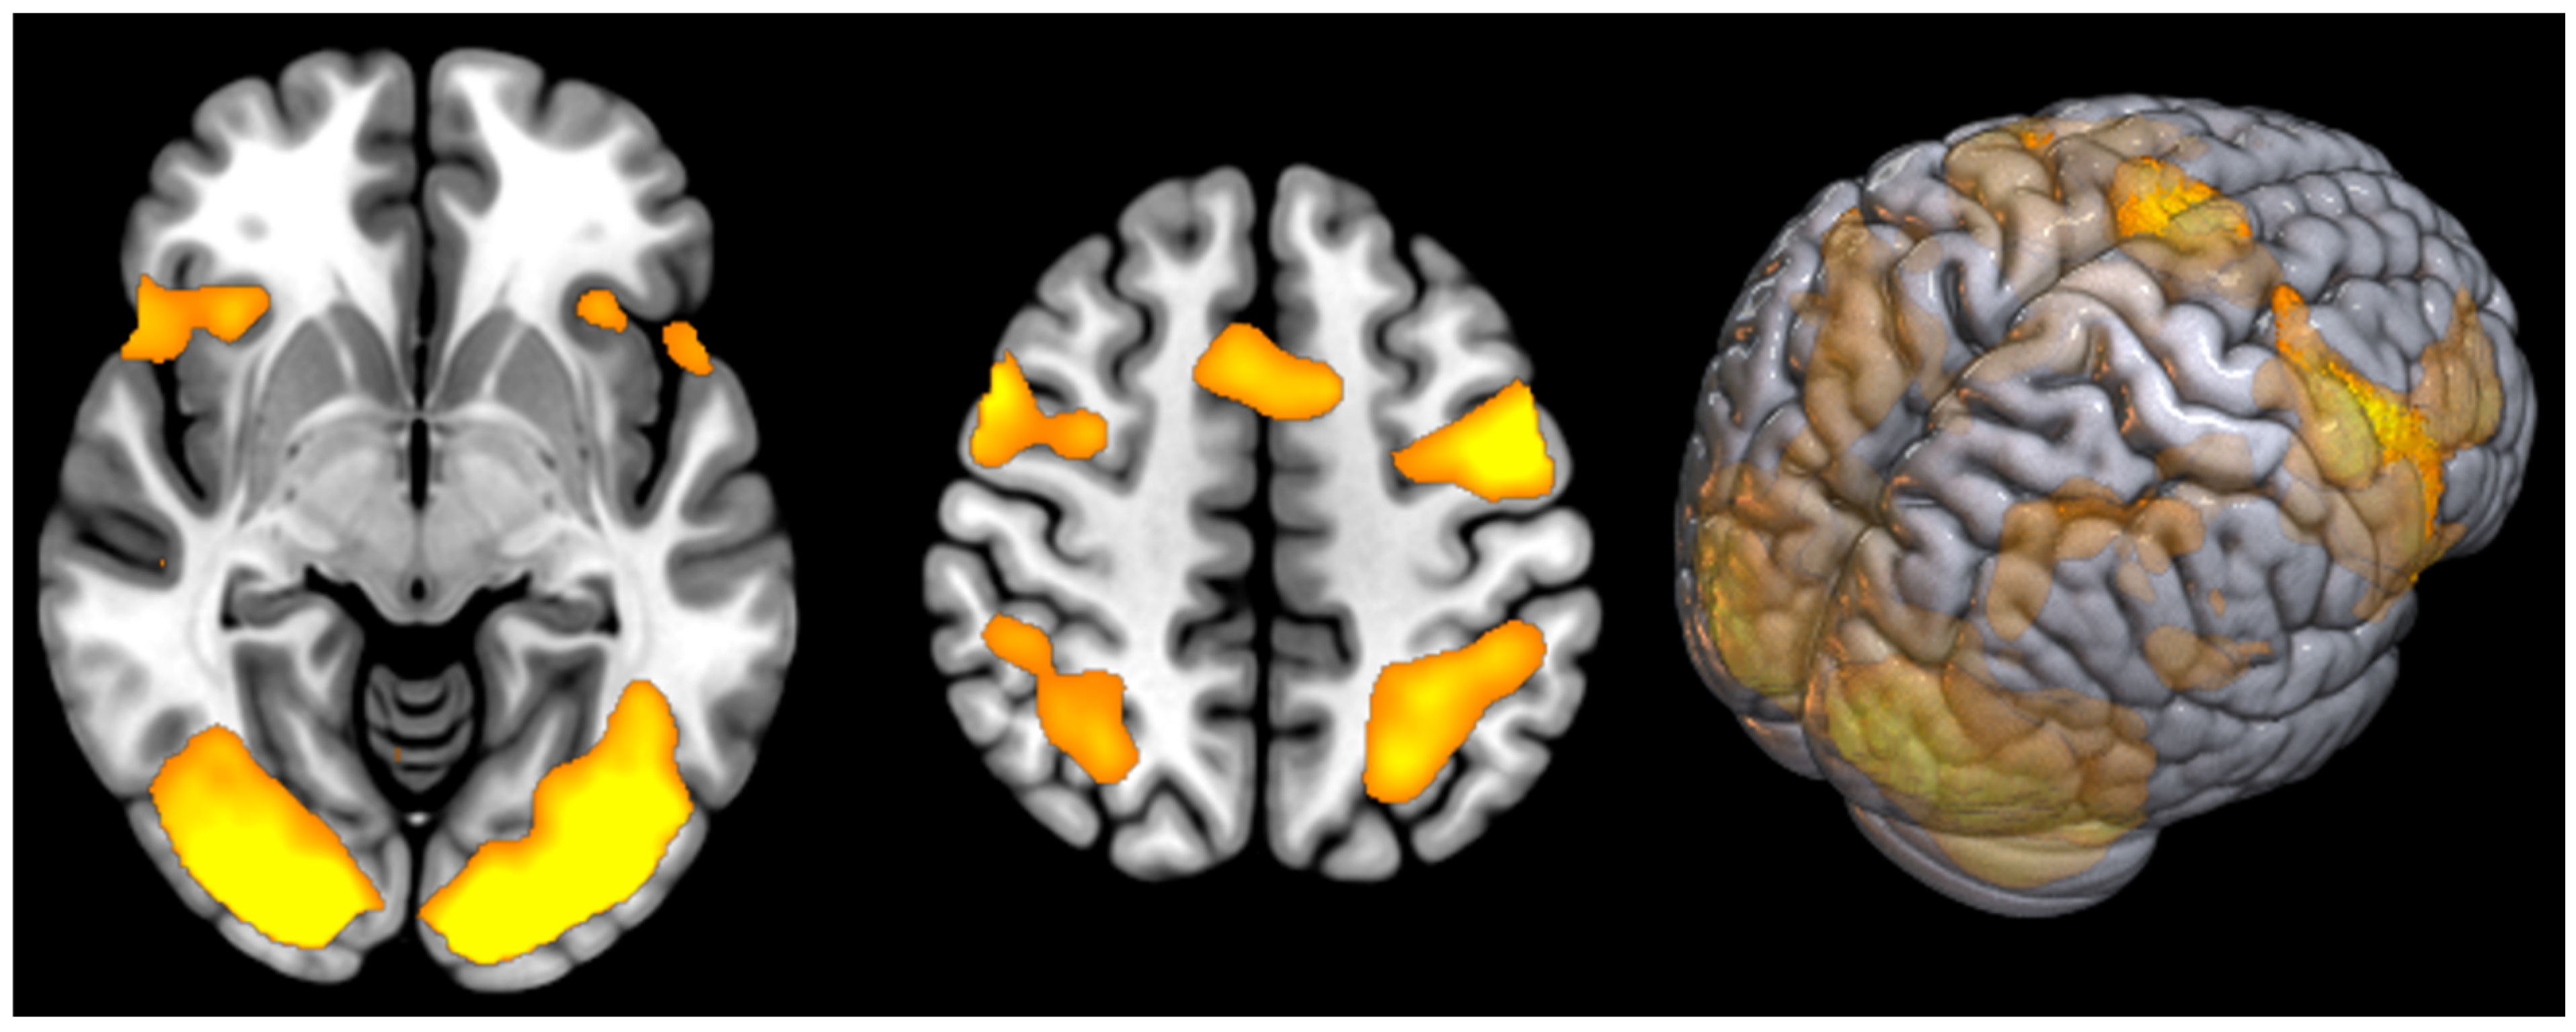

| T | PFWEcorr | Number of Voxels | Peak MNI Coordinate | |

|---|---|---|---|---|

| Supplementary motor cortex | 10.98 | <0.000 | 1002 | 2 8 58 |

| Occipital cortex (Fusiform gyrus) and Cerebellum Posterior Lobe (L + R) | 16.96 | <0.000 | 13,405 | −26 −86 −16 |

| Precentral gyrus (L) (BA6) | 14.38 | <0.000 | 1739 | −48 −2 46 |

| Precentral gyrus (R) (BA6) | 10.73 | <0.000 | 2186 | 52 14 44 |

| Parietal Superior Lobule (L) (BA7) | 9.21 | <0.000 | 1066 | −24 −60 46 |

| Parietal Superior Lobule (R) (BA7) | 8.43 | <0.000 | 315 | 28 −58 46 |